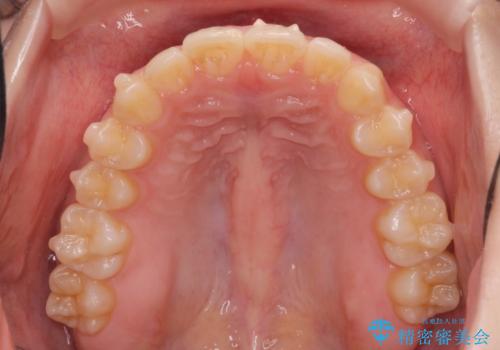

- 突出感のある、前歯の矯正治療を求めて来院されました。

軽度な突出・ガタつきを26枚・約半年の矯正治療期間で計画するインビザラインモデレートプランで治療を始めて行きます。

約半年といった短期間で、前歯の角度やガタつきを改善することができました。